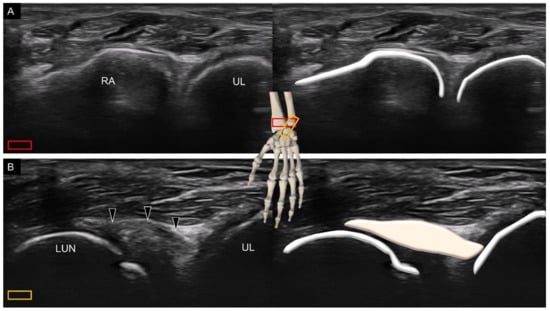

2. Sonoanatomy of Carpal Bones